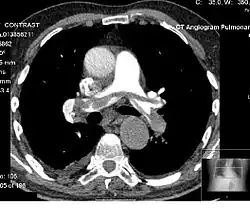

Vascular Imaging

Computed tomography angiography (CTA) is a type of contrast CT to visualize the arteries and veins throughout the body.[111] This ranges from arteries serving the brain to those bringing blood to the lungs, kidneys, arms and legs. An example of this type of exam is CT pulmonary angiogram (CTPA) used to diagnose pulmonary embolism (PE). It employs computed tomography and an iodine-based contrast agent to obtain an image of the pulmonary arteries.[112][113]